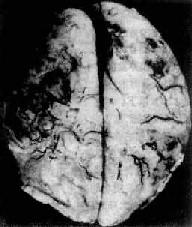

脑脓肿的发展规律和形态与全身其它器官的脓肿相似。急性脓肿发展迅速,境界不清,无包膜形成,可向四周扩大,甚至破入蛛网膜下腔或脑室,引起脑室积脓,可迅速致死。慢性脓肿边缘毛细血管纤维母细胞(源于血管壁)增生明显,并伴有淋巴细胞和巨噬细胞浸润,形成炎性肉芽组织和纤维包膜,境界清楚。脓肿周围脑组织水肿明显,并伴有星形胶质细胞增生(图16-12)。

慢性脑脓肿

图16-12 慢性脑脓肿

右侧颞叶的脑脓肿与侧脑室相通